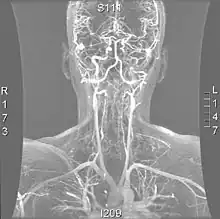

| Vertebral artery dissection | |

![]() | |

| Arteries of the neck, with arrows indicating the right vertebral artery | |

| Diagnostic method | Computed tomography angiography, magnetic resonance angiography, invasive angiography |

More modern methods involve computed tomography (CT angiography) and magnetic resonance imaging (MR angiography). They use smaller amounts of contrast and are not invasive. CT angiography and MR angiography are more or less equivalent when used to diagnose or exclude vertebral artery dissection.[18] CTA has the advantage of showing certain abnormalities earlier, tends to be available outside office hours, and can be performed rapidly.[1] When MR angiography is used, the best results are achieved in the T1 setting[2] using a protocol known as "fat suppression".[1][2][3] Doppler ultrasound is less useful as it provides little information about the part of the artery close to the skull base and in the vertebral foramina, and any abnormality detected on ultrasound would still require confirmation with CT or MRI.[1][2][3]